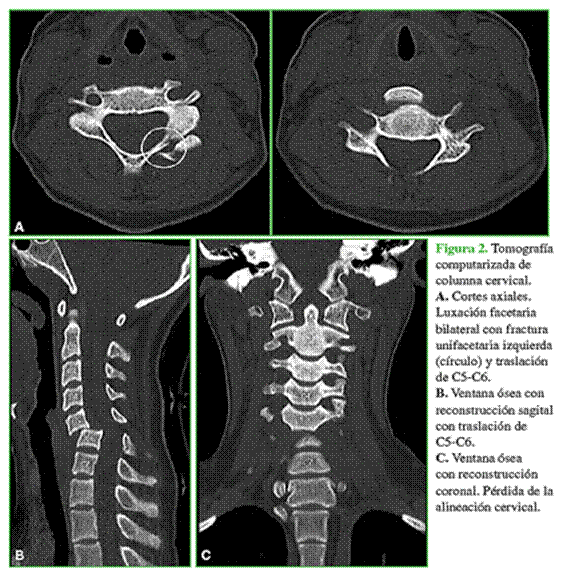

En la tomografía computarizada de columna cervical (Figura 2) en ventana ósea con adquisición axial y reconstrucción sagital y coronal, se visualiza una anterolistesis de C5-C6 con luxación facetaria bilateral y una fractura facetaria unilateral izquierda.